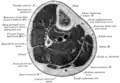

Secção transversa no meio da perna.